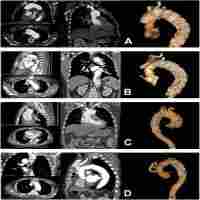

| Abstract | An aberrant right subclavian artery (ARSA) is an extremely rare congenital anomaly that forms during aortic arch development. Most reports of thoracic endovascular aortic repair (TEVAR) described an ARSA in the right aortic arch, but it is rare in the left aortic arch. We present the case of a 66-year-old man who underwent total arch replacement because of acute type A aortic dissection. An outpatient follow-up examination revealed that the aortic diameter enlargement exceeded 60 mm because of false lumen entry from the ARSA. Therefore, surgical intervention was planned. TEVAR, ARSA embolization, and bilateral axillary bypass surgery were successfully performed for a chronic dissecting aortic aneurysm for which the ARSA was the inflow route. He was discharged 12 days after surgery. Four years later, no enlargement of the aneurysm diameter was observed. TEVAR is a minimally invasive and useful treatment option for chronic type B dissections with an ARSA associated with the left aortic arch; however, patients with an ARSA have fragile blood vessels and require careful follow-up. |